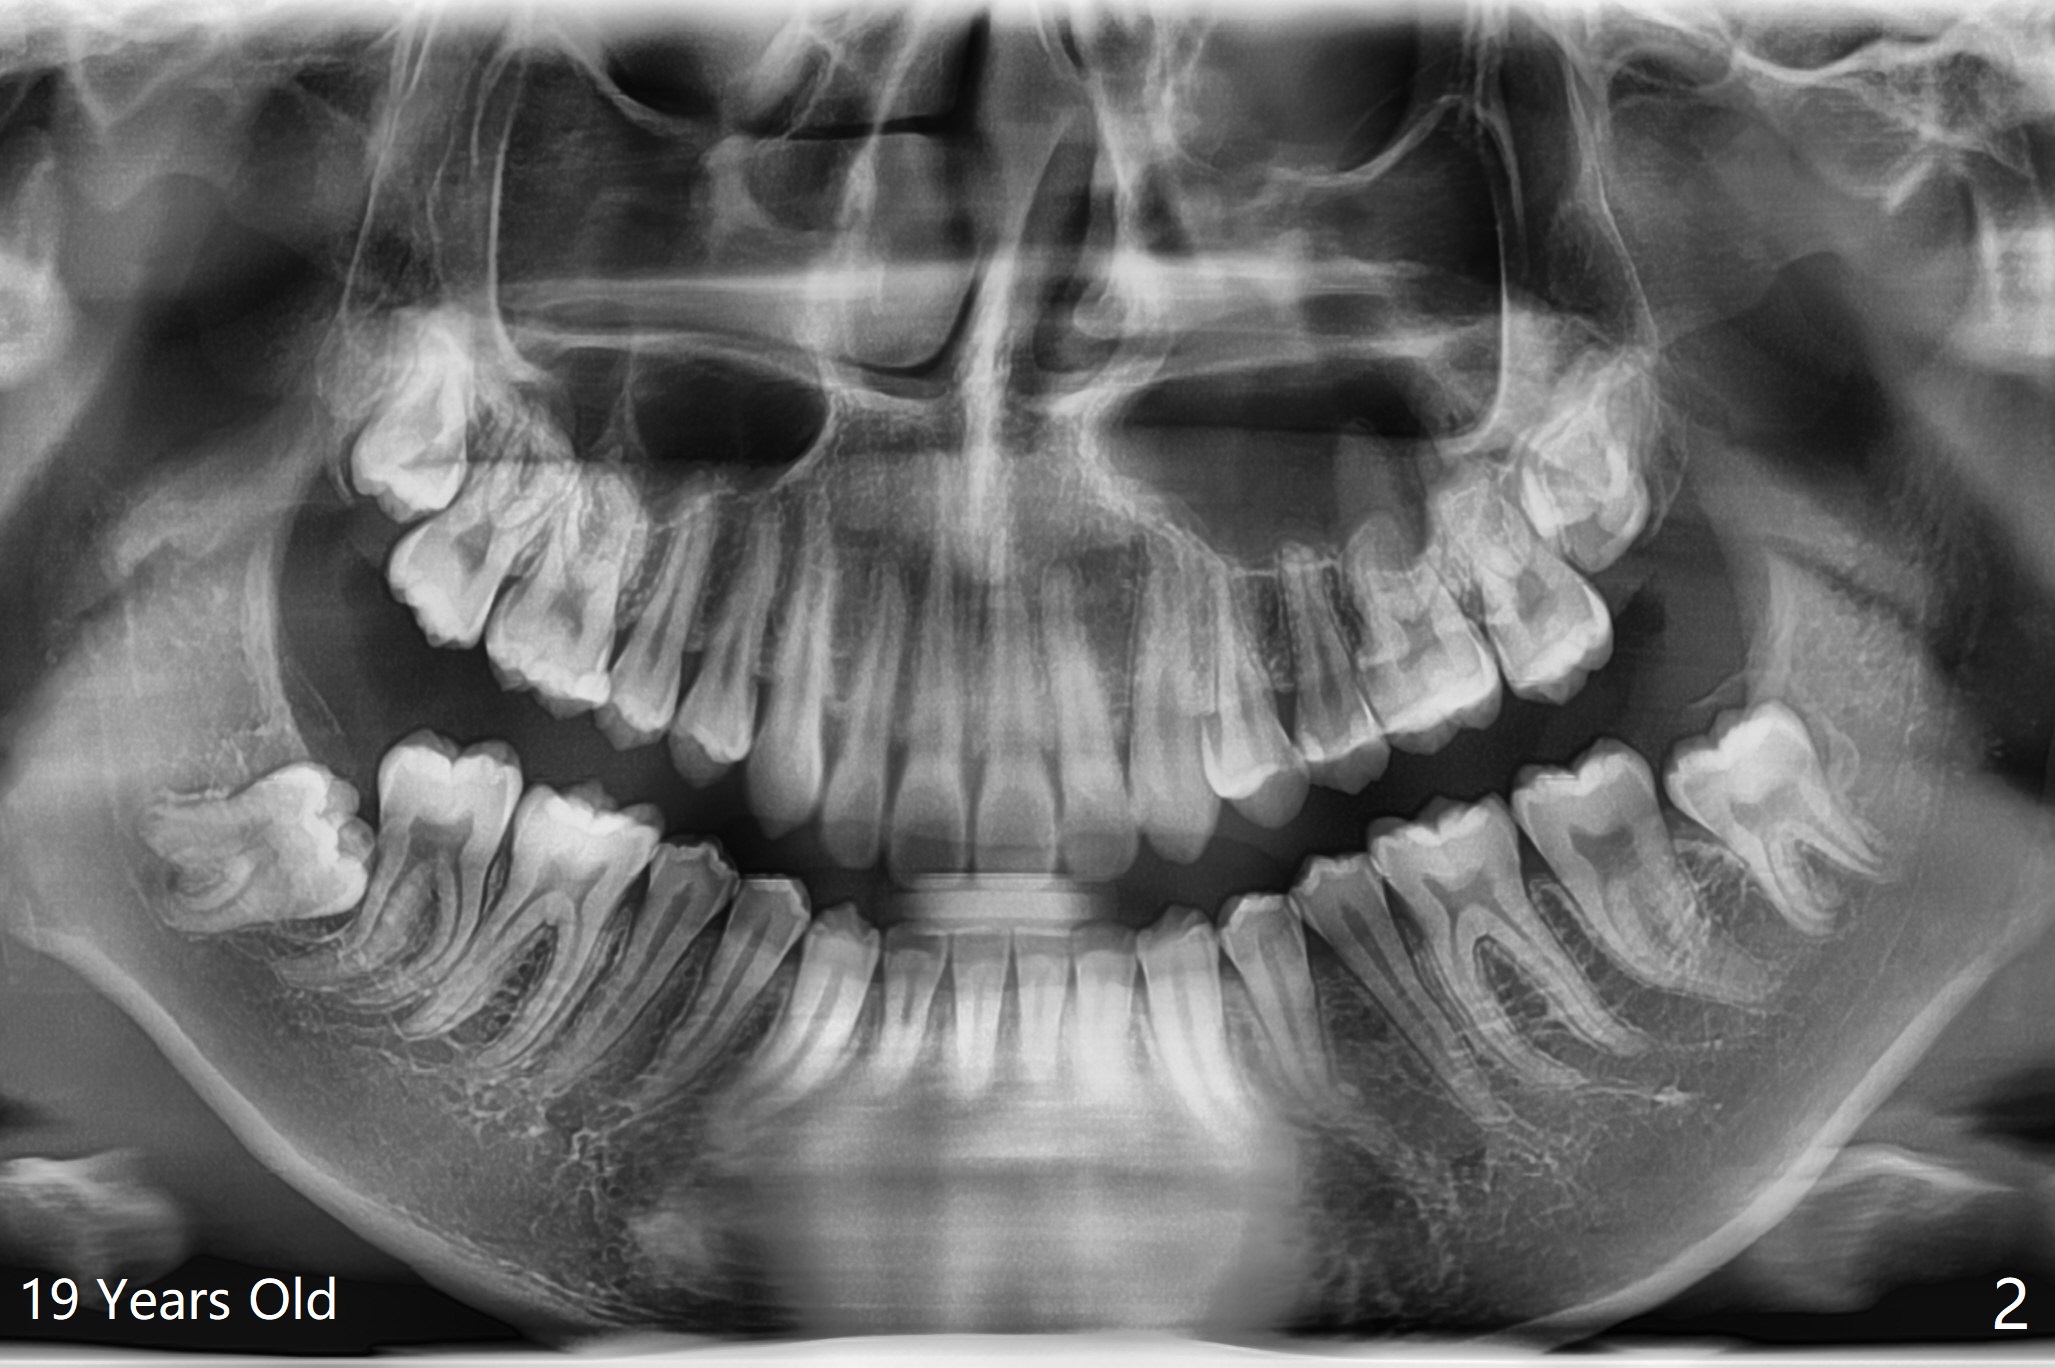

A 19-year-old man returns for #1,16,17 and 32 extraction (Fig.1,2). Because of horizontal impaction of #32 and no bone #31 distal post extraction (Fig.3 *), 3D bond (.5 cc) will be placed in the mesial socket of #32 (Fig.4 red), while Osteogen plug (1/2 (O)) in the distal one. Since there is no bony defect between #17 and 18 after extraction (Fig.5 *), a piece of Osteogen plug (cut half apical) will be inserted in #17 socket, whereas 2 small pieces of Osteogen plug placed in the apical portions (triangle and spindle shaped). Take posterior panoramic X-ray postop (bitewing type, CT format, not XV). There appears bone formation in the socket 5 months postop (Fig.10,11).